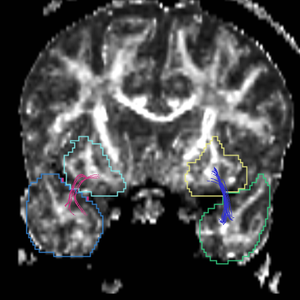

Region

caseD00917

caseD00920

caseD00924

caseD00928

caseD00935

caseD00936

caseD00938

caseD00939

caseD00940

Uncinate Fasciculus

Internal Capsule

Fornix

Cingulum

Arcuate Fasciculus